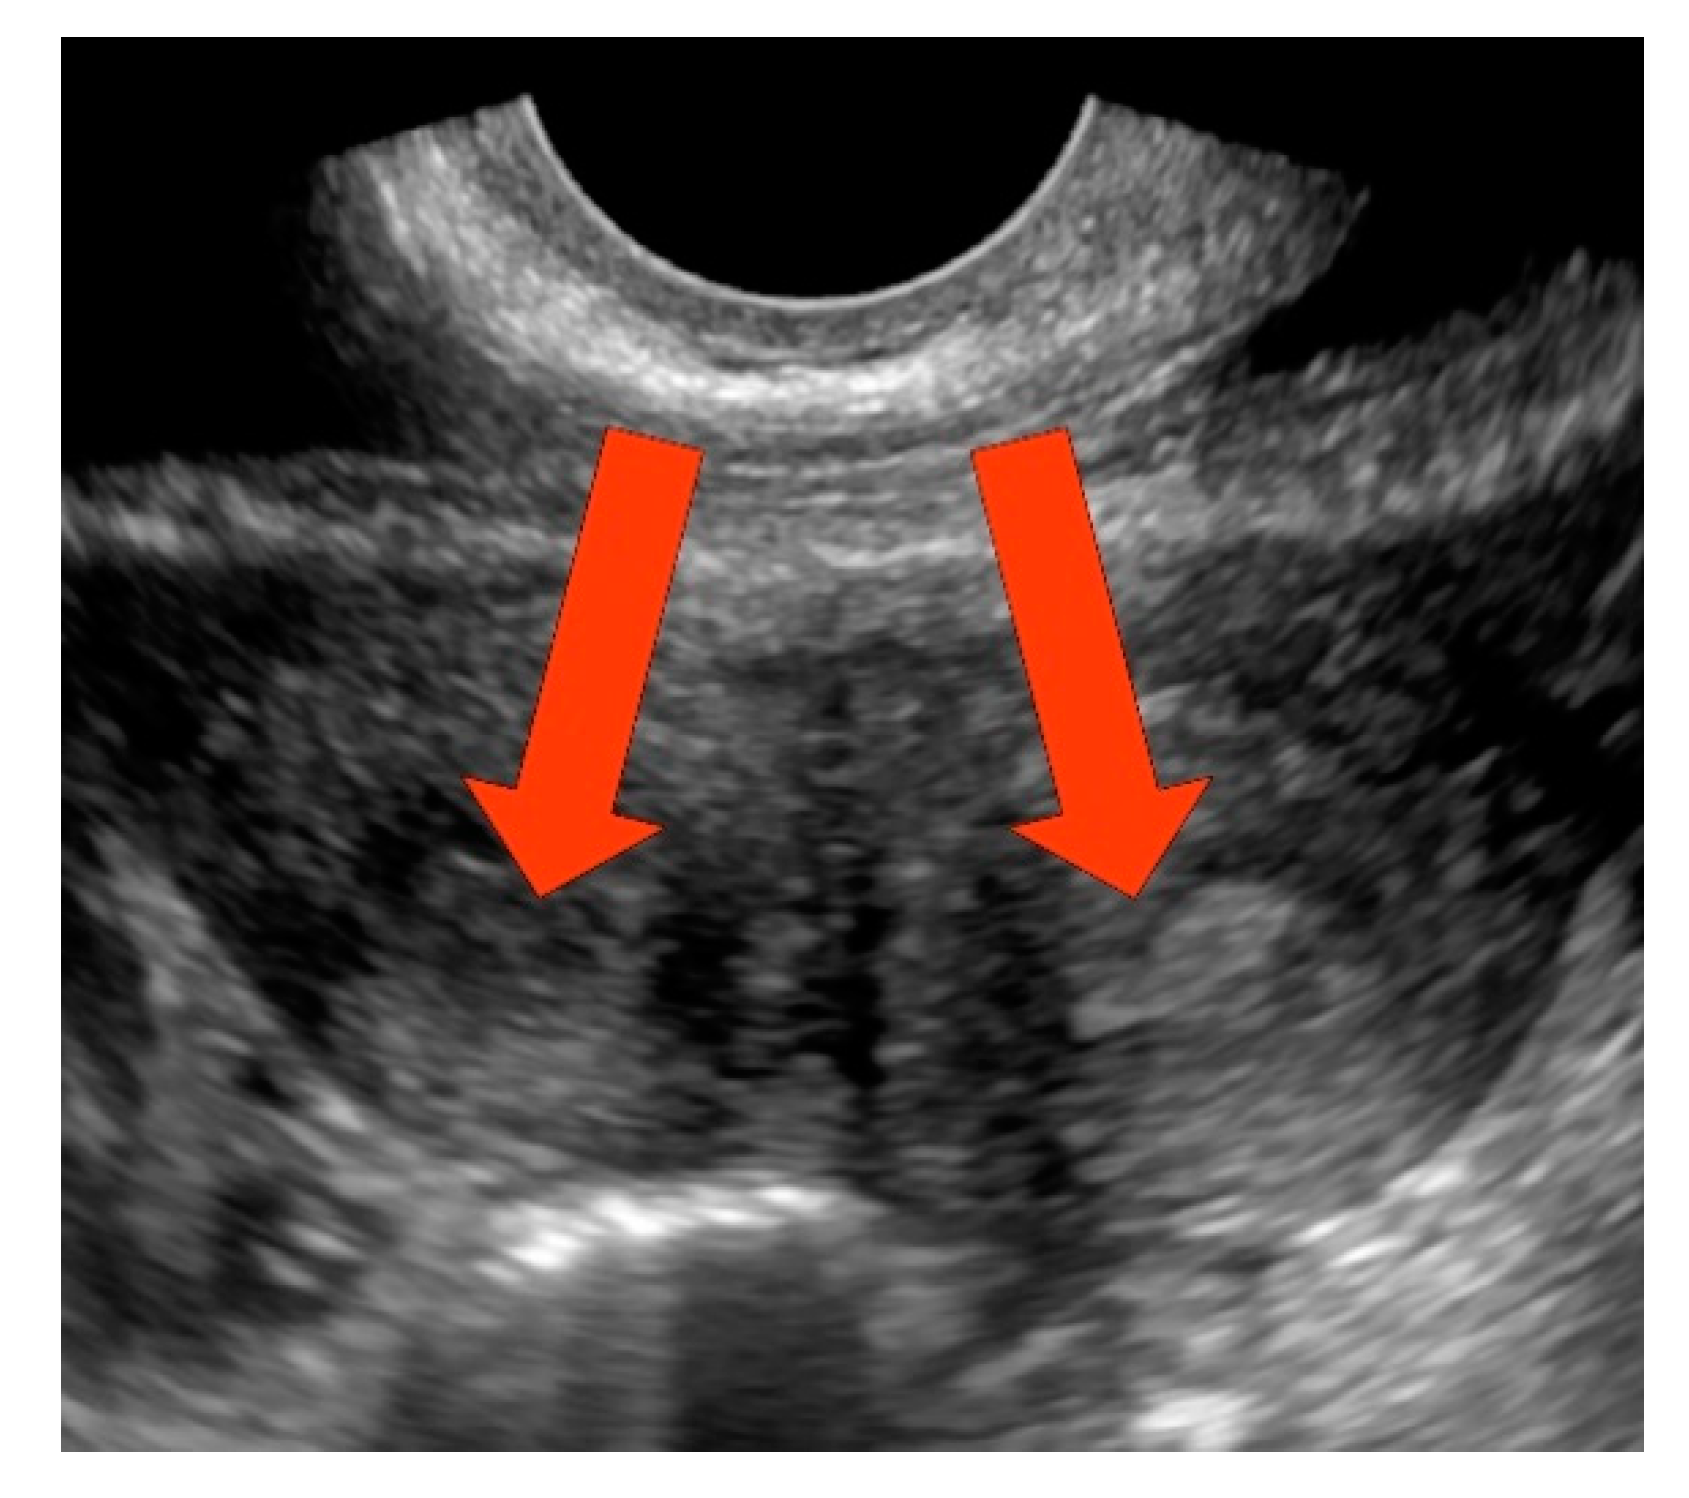

| 17-year-old | 17 years | 13 years | Acute lower abdominal pain, dysmenorrhea | Vaginal mass, pyohematocolpos, pyohematometra | L/L | Laparoscopy, vaginal septotomy, resection of vaginal septum, extension of hemivaginal entry (twice) |

| 13-year-old | 13 years | 12 years | Polymenorrhoea, dysmenorrhea | Vaginal mass, hematocolpos | R/R | Laparoscopy, vaginal septotomy, resection of vaginal septum, extension of hemivaginal entry (twice) |